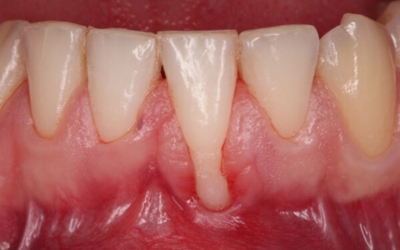

사랑니는 치아 중 아래 위로 가장 안쪽에 나오는 어금니입니다. 사람마다 사랑니가 4개가 나는 경우가 있으며 하나가 나는 경우가 있으며, 잇몸이 붓고 아플때는 사랑니가 근처 어금니를 건드리는 옳지 않은 형태로 자라고 있을 확률이 높다고 합니다.

옳지 않은 형태로 자라는 사랑니는 초기엔 잇몸이 붓는 정도이지만, 나중에는 근처 어금니를 썩게 만들고 사랑니와 멀쩡한 어금니까지 통째로 발치하게 되는 불상사가 생길 수 있습니다. 사랑니의 경우 잇몸 내부쪽으로 매복해 자라는 경우도 풍부하기 때문에 치과에서 사랑니 유무를 확실히 확인할 수 있습니다.